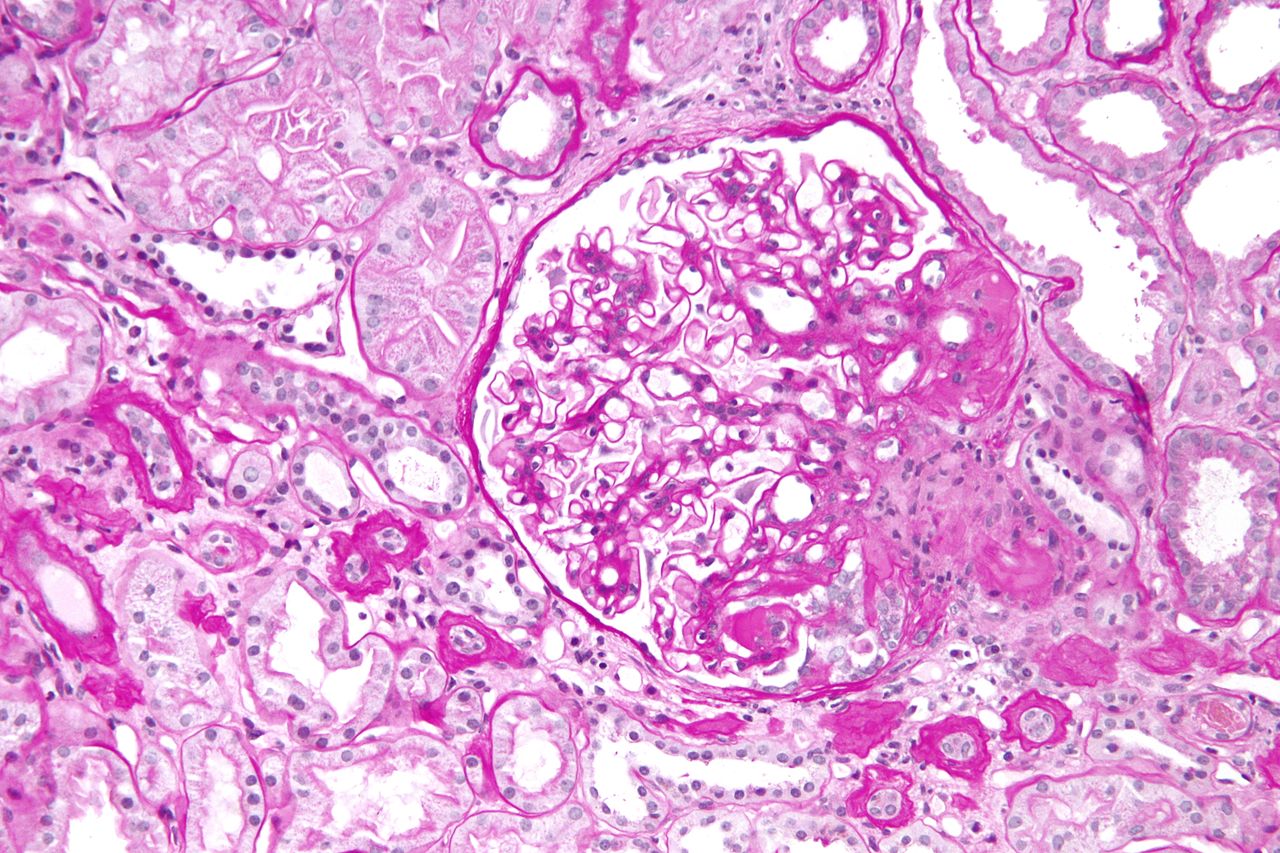

Kidney Biopsy of the Month Light Chain Cast Nephropathy Renal Fellow Protein In Urine Kidney Biopsy Why would i need a kidney biopsy? Persistent blood in the urine. During a biopsy, a doctor takes a. a kidney biopsy may be recommended if you have high or increasing levels of protein in the urine or if you have. a laparoscopic approach or a radiology interventional procedure through the internal jugular vein may be. but. Protein In Urine Kidney Biopsy.

Kidney biopsy in light microscopy of the patient (PASM staining Protein In Urine Kidney Biopsy a laparoscopic approach or a radiology interventional procedure through the internal jugular vein may be. kidney biopsy — your doctor might recommend a test called a kidney biopsy. a kidney biopsy may be recommended if you have high or increasing levels of protein in the urine or if you have. another name for a kidney biopsy. Protein In Urine Kidney Biopsy.